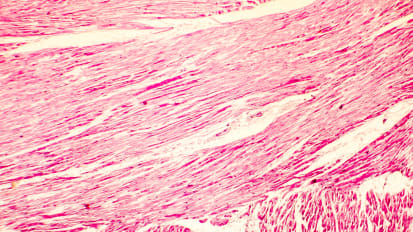

Chapters Transcript Video A Programmatic Approach to Lipid Management in 2023 Dr. Talreja details the epidemiology and pathophysiology of dyslipidemia. I'm honored to be able to talk to you about this topic. A programmatic approach to lipid management in 2023. And I know it's only 2022, but like a good chess match that has a beginning, middle and end game. I've crafted these slides to sort of tell the story of where we are and where we're heading before I do that. I wanna give a quick moment of recognition to the trainees who gave talks at this year's Heart of Innovation program. They were recognized during the program, but our time schedules were a bit messed up. There were a tremendous series of talks from a number of our trainees. They did a fantastic job and I can't wait to see what next year is gonna bring, calling out our 1st, 2nd and tie for third place winners who are getting cash awards. And uh, and the joy of recognition for success, um, kudos to all those and those of you listening as trainees, pay attention to next year's Heart of Innovation Conference. Another chance again, amy will get together with all you guys afterwards with your certificate book and uh, and the award. So part of Innovation again this coming year, I'll launch right into my topic. And I'm gonna tell you, I'm gonna talk really fast. I have a whole lot of slides and I kept trying to condense them and then add more and condense them. This really should be two grand rounds. But since we're ending the year with this one, I only have space for one. These are my disclosures, they're available on the websites as well. So I started with an interest in lipid ology probably a little over a decade ago, one of my partners in cardiovascular associate steve jones lured me into boarding and lipid ology and as I think of the sort of tale of two cities approach to the world. These are the two differences I see in my clinic I get referrals of patients with severe aortic stenosis for trans catheter based aortic valve replacement. Those patients typically have a lot of information at their fingertips and they come in knowing exactly what they want. They've read everything and they know where they want to go. In fact were often the ones sort of slowing them down and saying, well we have to think about surgical options. You may not actually need a valve replacement at this point. So, good job learning. But maybe we're not there yet. The opposite is the lipid clinic where the typical consult is a patient who has read this among many books and is skeptical of what is again, clearly lifesaving technology. That has a tremendous value proposition. And it's a real tragedy because as a result it limits what we achieve in prevention, which really is the key at the end of the day. So today we're gonna talk about some epidemiology and path of physiology of dis lipid e mia. We'll talk about lifestyle options and specifically the tremendous opportunities that exist in our community for really changing the course of a disease trajectory for atherosclerotic cardiovascular disease. We'll talk about pharma co therapy options and I'm gonna blitz through quick look at data and what's available and what's new integrated throughout this and especially at the end will be guidelines. And then we'll talk about the lipid program where it is and where it's going. So atherosclerotic cardiovascular disease in 2020 is estimated to affect 30 million Americans 19 million. So two thirds roughly are on statin therapy for some form of this disease entity. 15 million receiving statin therapy were not at the A. C. C. H. A. Recommended goal of an L. D. L. Less than 70. So shocking in this era that we really have so much. We're not even at the halfway point in terms of achieving what we set out as our goals. Obviously atherosclerotic cardiovascular disease is a heterogeneous group of diseases. Those of us in cardiology so often think of coronary disease dancing ACUTE. M. I. Semis and so forth. But stroke P. I. A. And P. A. D. Including aortic disease are really a part of this uh different spectrum of disease. Over the last three decades we've seen a tremendous improvement in cardiovascular mortality. Unfortunately over the last most recent decade of those 3 to 4 decades we actually seeing now an increase in deaths attributable to cardiovascular disease independent of definition. Some of this is perhaps catch up you know no one's immortal and so as we make people live a decade longer eventually we're going to run the course on that time. But some of this is a more complex disease process and there's a lot of other factors this slide calls out in diabetics in particular. We've made tremendous inroads with new therapies and the last time I gave a grand rounds on this topic, Elias carriage from the VMS endocrinology department joined me and he talked about management of diabetics after I talked about methodology. Um what we see again and again is even with the newest therapies, you know think of S. G. L. T. Two inhibitors GLP one ras and other therapies. We have insulin pumps. A diabetic patient still has a 1.5 fold increase in the risk of cardiovascular death compared to the general population leaving that as a particularly vulnerable population. The reason is, and we know the molecular level of what's going on in quite some detail. Amazingly enough, I will say of all the boards I've taken the lipid boards were the most nitpicky and hardest to understand. And part of it is the path of physiology we're talking about here is so complicated that even when you sit down and try to draw out everything we know there are huge gaps in the mechanisms that work. But what we do know is a probie bearing lipoproteins. Think of LDL and particles like that are really where the action's at in terms of creating inflammation in the vessel starting the process of plaque accumulation and going on to create ultimate calcification. We know a lot about lipid metabolism. The average american consumes 200 to 400 mg of cholesterol a day. The average american produces between 612 100 mg of cholesterol a day. So bad diet plus good genes or good diet plus bad genes leave us with some variability in how patients respond. We know HDL can be beneficial. We know LDL and the particles like it can ultimately lead to plaque accumulation. And ultimately, If you want to think of this in a fairly simplistic fashion, it's LDL level, circulating LDL times the number of years of exposure to it. That equals your total plaque burden and causes atherosclerotic cardiovascular disease. We can't affect time directly, but we can get patients on good therapy and give them a long run on that good therapy to try to prevent accumulation of plaque and that's really the goal of everything we're talking about in the next 40 minutes. So first and foremost, let's talk about lifestyle modification. This is clearly underutilized, although we've made a lot of inroads in this, calling out the 2022 American Heart Association statement on the comprehensive management of cardiovascular risk factors for adults with type two diabetes. We see that lifestyle modifications are the first thing we think about quitting smoking, exercising, eating right, losing weight. Then we think about social determinants of health. We think of cardiovascular imaging, I think in this era we still massively underutilized, fairly inexpensive tests. Think of coronary calcium scores. Think of cT imaging. We have great stress testing and for those patients that needed cardiac catheterization. But compared to a decade ago, there's there's obviously a lot of ways to pick this process up early in the game. And then we have a great number of medications, especially in the general population and in diabetics that can impact this disease process quitting smoking. I'm just gonna show this slide enough said critical, critical um dietary patterns. This is from an A. H a publication plant based diet will call out specifically as what recognizes one of the healthiest diets out there now. Of course no diet is effective if a patient is not going to follow it. So there are other opportunities available for us. And we've done study work on some of these, I will say, unfortunately, the worst diet out there fits with our geographic location. The southern diet is really the one that is known to increase the risk of cardiovascular disease and heart failure. Physical activity. Any level helps increasing mets, especially up to uh the relatively moderate level has a dramatic impact on all cause mortality. And that's why cardiac rehab programs are so useful. It's tough practicing cardiology in your local community for those of us that want to go out and grab some fast food, you have to hide if you're a cardiologist, I don't get there much. But among the billions and billions served. I try to be not in that pool too much and most of our patients need to do the same. So years ago, almost a decade ago we did a study. Many of the folks in this room were part of this are supported one way or another an investigation of four commonly used diet, plant based mediterranean, paleolithic and dash diets. I showed this in a forum here, but it's been about a decade. This is collaboration between our area and the University of Virginia. We offered 100 patients that self selected their their arm. Four commonly recommended diets and what we saw was interesting just quickly calling out everyone lost weight or every group lost weight anywhere from 4 to 5 up to £12 over a period of 60 days. B. M. I improved blood pressure improved pretty remarkably. This is what you would expect from one or two medications. An average blood pressure drops systolic a between 10 and 15 mm of mercury. For patients that complied and calling out some lipid changes. We saw pretty impressive reductions in everything from triglycerides to LDL, including highly specific markers like L. D. L. P. You see in this, the vegan group really had the most remarkable decrease in LDL. P. 100 and 40 point decline. Diet is extremely effective. Now this was a decade ago. What about since then I'm gonna come back to our rehab programs. I've worked with them to get some of the data from our patients locally over the last quarter for those patients who can't get where they need to be or starting too late in the game for diet to be sufficient pharma co therapy becomes important. There are a lot of trials in this spectrum. These are great trials. We participated in a lot of them and we'll talk about some of the key ones as we look at what's going on. So if we think about lipid lowering agents, our mechanistic understanding of what's going on has allowed the development and testing of specific agents and this is from the journal American College of Cardiology. There are five specific mechanisms called out here. Number two is our H M G. Co a reductase inhibitors statins, very effective, very underutilized patients are very well aware of the potential side effect mechanism. And importantly, even with statins which are the 1st, 2nd and 3rd line therapy, a lot of patients we looked at the numbers earlier cannot get to their target therapy, whether it's related to compliance or insufficient potency. One above the status in the same pathway of production of cholesterol within the parasite is a teepee citrate lies we have a blocker for that which works upstream of statins and can be used with them. That's empathetic acid. Number three. The NPC one. L one receptor is where um I've works and we'll look at that Number four is through interactions with the pcs K nine protein. And that's where we have new injectable agents that can act directly on that. And then today we'll talk about one of the newest editions which actually works on blocking the transcription of M. RNA for pcs canine production and we'll call all those out and the mechanisms to come. So first we always have to think first and foremost in pharma co therapy about statins. There is absolutely no uncertainty whatsoever about the effectiveness of statins in reducing cardiovascular disease. This is the largest meta analysis of almost 100,000 patients showing reduction in every important endpoint all cause mortality, coronary mortality, M. I. C. H. D. Death stroke and major vascular events. Of course there are some patients that have difficulty tolerating these agents but there's absolutely no question that the value proposition, generic, inexpensive costs with tremendous benefit is there. And so it's incumbent on us to try multiple statins at the highest doses patients, patients can ultimately tolerate in all patients. And again, if you look at these trajectory curves, you've all seen many times before whether we're talking about the secondary prevention curve on the top which has a steeper benefit curve or the primary prevention group which has a slightly shallower benefit curve. There is zero questions across all populations as we lower LDL with statins and actually many non statin therapies follow the same curve. But in this slide we call out, lower is better with statins and we really have to be aggressive about it enough. Said I know this is obvious everyone knows it but it's important to call out again. Where that leaves us though is if you look at the major trials of status in every single trial concorde only statins lower event rate, but there's a pretty high residual event rate in each of the trials as well. You see statistically significant benefits. But we see a 25 to 40% residual risk for recurrent events across every trial. Every population we've looked at and that's the group. We have to do more for so many years ago we were in the improvement study that tested the addition of a on top of statin. There's a lot of things you can criticize. But ultimately what that trial showed us is effectiveness of um I've it took about seven years for the curves to reach statistical significance. It takes a while. But the group on combined as a team I've and statin does better with the number needed to treat a 50 that's statistically significant. And that's why again, is another generically available agent. There is a clear utility for this and we'll look at where it falls in the guidelines more recently, the introduction of psychedelic acid has given us another mechanism to affect lipid production within the liver. Some potential benefits of this are it works in a different area than H. M G co a reductase inhibitors, although it's in the same basic pathway, it is a pro drug that has to be converted to its active element. And interestingly in skeletal muscle there's no conversion enzyme. So in theory potentially less skeletal muscle concern with the OIC acid than we see with statins. So gives us one other option and studies have shown us. While outcome studies are still pending, we have clear data that shows about 15-20% reduction in the largest trials trials compared to placebo for the addition of the OIC acid to a satin. And when we look at the combination of a demise and um and and and talk acid together which is one combination pill, we can get up to a 40% additional reduction. So another therapy, again, no hard points yet, those trials are ongoing but this can be effective in patients either statin intolerant or can't get to their max benefit. Everyone here knows about PCSK nine inhibitors. Again, really, a remarkable example of the benefits of understanding molecular level pathways from initial identification of the relevant genetics and populations out there to FDA approval and outcome studies, we're looking at a period of under 15 years to get this therapy available to us. The idea is P C S K nine is an enzyme our body produces on the left. It's the things that looks like cheetos and orange color and what they do is when they couple together with an LDL particle and an LDL receptor, the PCSK nine results in degradation of that LDL receptor, you destroy your own LDL receptors. They finessed over time. Each LDL receptor recycles about 100 and 50 to 200 times. And this is the natural sin essence mechanism. There are people who genetically don't make pcs K nine and they have a lot of extra LDL receptors because they stay in circulation and they work longer. They tend to have low LDL. And so we've replicated this with available mechanisms based on current molecular biology. Um this is lucca mob one of the available ones monthly or every two week injectable agents available multiple trials in the Oslo program that show us very effective reduction in LDL cholesterol. The LDL has dropped by about 50 to 60% across studies and it's a durable effect with potentially a monthly injection for this. Initial costs were high. Those costs have come down as coverage has improved. And now, in addition to proving that we can get a much larger number of patients to their LDL goals, we see outcomes. This is the LDL cholesterol goals. If you look at the LDL goal on the left of an LDL less than 100 we see that in the standard care therapy which includes statins, diet nutrition and the Hamid, about a quarter of patients are getting to that LDL target of less than 100. If you're looking for the LDL target of less than 70 it's under 5% of patients with traditional therapy in that high risk group that get there when you add PCS canine inhibition onto that, it's not 100% but we're getting 90% now to the target of less than 100 and three quarters of patients to that target of less than 70. So tremendous impact on LDL cholesterol and LDL concentration. For a long time. I think many providers wanted to see the outcomes data. We do have multiple trials showing us that correlates with what we would expect an improvement in cardiovascular outcomes. Hard outcomes including death, M. I. And unstable angina and outcomes including coronary vascular ization, stroke tia and even heart failure. You see standard of care alone is effective compared to the general population, but when you add in the PCSK nine inhibitor on top of that, you have a very significant improvement in overall outcomes. I have talked fast. I've gone through a lot of the things that I think have been with us through the last iteration of the guidelines. The 2018 american Heart Association and american College of Cardiology guidelines. So I'm gonna slow down a tiny bit as I go into newer therapies because I think this is the area where folks are a little bit less familiar, just recapping, we've talked about the disease process the burden of disease and deficits in our treatment strategies. We've talked about why lifestyle modification is critically important as the first step and we have to keep coming back to it. It's a battle that's never won. It's like keeping my house clean just after I get it all clean, it seems like it's starting to get dirty again and I got to start from scratch. And then we've talked about a lot of the the conventional therapies we've had available from statins to and there's older ones that are available to the data points are a little weaker for some of those but they are in the guidelines in the interest of time. I've left them aside and then we've culminated with the PCSK nine inhibitors. So now where science has taken us next is the RNA based therapies and I'll give a light dusting of the surface of this topic. There's a lot more to come. And the world of lipid ology is where there's a huge amount coming in this arena as we think on the far right of the slide about M. RNA back to our our days of uh of biology and biochemistry. So M. R. N. A. Is what's transcribed or transcribed from D. N. A. And translated into protein. M. R. N. A. Is sort of the working blueprints that allow our bodies to produce the proteins that actually cause things to happen. And so when that M RNA is translated, we make things like for example PCS canine. We talked about where PCS canine sort of works against us by degrading our own LDL receptors. There are two types now of commonly used RNA therapy. Moving to the left side of the slide here. Anti sense RNA are double are single stranded RNA that are a complement to the other side, making a double stranded um um molecule. So remember DNA double stranded, we transcribed one of the strands and make a single stranded messenger RNA. Back thinking back to A T. G. C. And all those things. If we make a compliment to that we'll now use that complement in circulation if you can get it into the cytoplasm to bind with the matching M. R. N. A. So you can target a specific blueprint specific M. R. N. A. And gum up the works so that you're not going to produce that protein. So you can imagine how that can be used to stop the body from making something like C. C. S. K. Nine. There are also small interfering RNA. These are actually double stranded RNA. Again you have to get them to where they have to go but they're going to ultimately gum up that process of translating the M. RNA into the protein. And so these are techniques we're gonna see more and more, the durability is longer than with the traditional oral agent but these agents can be consumed orally currently although there's interesting work going on in that realm. So now we're gonna talk about in clustering and so PCSK nine inhibitors let's focus on the left side of the slide in a traditional human body. What's happening is our body is translating messenger RNA A making the enzyme PCS canine, releasing it to the cell surface. The pCS canine is coupling with an LDL particle and with an LDL receptor as that endorse it, toast the LDL receptor is destroyed and we lose a valuable tool for getting rid of cholesterol in our circulation. So PCSK nine inhibitors, the traditional ones we've thought about our monoclonal antibodies that once that PCS canine enzyme is released into circulation, destroy it, they bind to it and use our immune system to clear it. We're kind of getting to it after it's gone out into circulation. And obviously uh if you think about it we're never gonna catch 100% of them. So another effective technique which is where in clustering works is to use this M RNA technology to stop the synthesis of PCS K nine in the first place. Now again you're not going to stop 100% of it but you're gonna have less circulating PCSK A nine and as a result you're going to have more circulating LDL receptors. So the mechanism is very similar to what we're already familiar with with monoclonal antibodies to attack this. Some interesting differences are that this therapy is given typically after its initial loading as accused six month therapy which which opens up the opportunity especially in patients that are potentially less compliant to have every six month therapy that could be given potentially in the office on top of that it can be used in addition to the other therapies, including monoclonal antibodies to PCS canine we talked about in the Orion series of trials. This is one of the trials we see again a sustained and highly potent reduction in LDL cholesterol of about 50 to 60% once again. So yet another tool in our armamentarium here accused six monthly injections trying to keep an eye on my time as I go to. Alright, I'm making a good pace. I know I'm going fast. Um It is interesting as we think about this technology. There are a number of RNA based drugs in development in testing and we've already seen the first ones come available to us more coming. We've seen the effect on the far left for PCS canine antagonism and now we're looking at trials coming out which will be my next grand rounds in a year on a pOSI three on a po A And also on and P. T. L. three. We'll talk a little about that in the in the time to come so we can impact multiple different lipoproteins and hopefully further affect this disease process where we still have residual risk left behind. It is interesting one question that often comes up is so what about triglycerides? What about HDL HDL therapies to date besides exercise, low doses of alcohol and uh cessation of tobacco use have been largely ineffective in improving mortality outcomes. So HDL is very difficult to figure out right now. Triglycerides. We know that if you look at epidemiologic data, high triglycerides correlate to increased disease risk. It's unclear whether that's causal or whether it's related to an other underlying disease process. But we'll come back to triglycerides. I could give a whole other grand rounds on that. I've included just a little bit because again looking at trials, there is some benefit there I mentioned briefly and PTL three. I also want to talk about um this uh this group of patients with homocide. FH those patients are rarer so if you think about it we have patients with familial hypercholesterolemia. That's a disease where the genes for the LDL receptor don't work well. Um Homocide FH is when a patient has two broken genes um There are five patients I follow in the lipid clinic in this region with homos. I guess FH it's rare. Heterocyclic FH is much more common. This disease process results in early mortality, catastrophic levels of disease. And there are many different criteria. We can do genetic testing for it. And what's complicated is there are a lot of genes involved. Some of them are the LDL receptors. Some of them are other things like a po B. And P. C. S. K. Nine. We can't identify them. All genetic testing is useful but can be expensive. There's a lot of stuff we have to test and the genetics are pretty interesting because you can have um double heterocyclic compounds. Heterocyclic or identical um home they can have two of the same broken gene or two different types of genes. Um Family members have to be screened. There has to be some form of genetic counseling and typically they have very high LDL. I'm not talking about their total cholesterol. Their LDL can be 400 to 600. And frankly any time you see someone on therapy who has an LDL greater than 300 you should think of this disease condition. These patients need the kitchen sink thrown at them. They need aggressive diet change. They typically need to be on 34 or five therapies. We often did L. D. L. A. For reasons for these patients which is inconvenient and difficult to arrange and not widely available. But recently a different mechanistic pathway. Different mechanistic pathway has been employed to treat these patients. And if we look at another injectable therapy avenue ca mob. This is a therapy that utilizes a different pathway. Now this is an oversimplified pathway. But let me explain what's happening on the far left. You see the liver is producing V. L. D. L. The LDL particles. Very low density lipoproteins are metabolized through like phases the lipoprotein lips. The red LPL and cecilia like paces the red E. L. Into the LDL remnants, intermediate density lipoproteins and then ultimately go on to form LDL. Which is what we typically think of in some genetic disorders, patients can have excessive levels of just the LDL itself. But typically if you think of the average patient in this pathway, it's the lie paises that push the particles along and there's this enzyme and PTL three and important like protein three that inhibits the life. Now if you now follow the circuit around so you go down to the bottom through the LDL LDL particles and you see those are taken up in the liver by the LDL receptors which are those spaceship shaped purple things on the bottom of the liver. So in a typical patient we secrete the LDL metabolize it, take the LDL back up into the liver and get rid of it. And that's where for example are PCSK nine inhibitors are so useful. Uh Right because they increase the number of LDL receptors. But now you imagine the poor patient who has nonfunctional LDL receptors, we can give them more of those receptors but they're not working in the first place. And so we're gonna have limited efficacy to just ramping up LDL receptors which is ultimately what statins zita, my psychedelic acid and all our forms of PCSK nine inhibition do. It turns out there's another way to get cholesterol out of circulation. We have V. L. D. L. Remnant receptors which are the green space ships on the side of the liver there and so there's a secondary mechanism completely independent of LDL receptors to get rid of these particles. And that's what does is it up regulates that the LDL receptor receptor receptor remnant uptake. What it does is it blocks the ndp TL three and through a complicated mechanism that's not entirely uh you know clearly laid out in this slide because it's super complicated. What happens is you get more V. LDL remnants taken up by those remnant receptors which are largely functional in these patients who have non functional LDL receptors. And what happens when you give patients this therapy This therapy is a once monthly therapy now it's not a sub Q injection, it's an infusion that's given. But what it does is it reduces LDL in these homocide FH patients another again around 50%. It seems like every time I show you a therapy I say it reduces LDL by 50%. That is kind of what the data shows. So with these newer generation of therapies this is approved for Homo ZegaS F. H. This is not for your hetero zygotes or other patients. Yet interesting trials will be ongoing but for that group of patients the unique mechanism makes absolute sense. And this can be again a really impressive add on therapy we still like to use the other therapies and those patients. And in fact this 50% reduction is on top of in the trials, I don't have enough time to go into all the data. But those patients who are largely on three or more therapies, including Pcs canine therapies um on a crisis on limited pied, which is an older therapy really isolated for those patients. And so now we've looked at a bunch of different, newer injectable therapies from PCS canine therapies to imply sarin now to even upthe map. And so the world moved ever forward with this. As with so many things, I think many times it's overwhelming to the average clinician out there who has, you know, 15 or 20 minutes to see a patient. Our staff does tremendous work to help us get preauthorizations and so forth. This is why in the slides to show you, I'll go over, we have the lipid clinic available for those patients who identify that needs some of these more aggressive therapies. Please do not hesitate to reach out to me or anyone on our team that can help and try to make this happen for patients. Last thing in terms of pharma co therapies I think has to be called out because it's been an area of controversy over the last decade is E. P. A. And D. H. A. Therapy. So we're talking about omega three fatty acids. We're talking about fish oil here. There are some plant based versions recent trials have made us suspect that there really is a difference between E. P A. And D. H. A. Both of which are the traditional omega three fatty acids, E. P. A. And D. H. A. Combined trials generally haven't shown a hard endpoint benefits. But to really important trials, the jealous trial and we'll look at reduce it shows specific reductions in cardiovascular endpoints on E. P. A specific formulations and there's some mechanistic reasons why that might work. But reduce it. Just to call out this trial looked at 8000 patients with pretty well controlled LDL and triglycerides of 1 35 to basically 500 with risk factors like diabetes for cardiovascular disease And what they showed that was impressive and consistent with the previous jealous trial is reduction in both the softer primary endpoints of CV death. My stroke and also unstable engine and revascularization. Those latter two make it softer but also of the harder cd det M. I. And stroke. You see statistically significant reductions. You see the p values are much much less than 0.5 and you see numbers needed to treat of 20 to 30 in this situation. So kind of a breath of life back into thinking really about the appropriate patient with that moderate elevation of triglycerides for using E. P. A specific formulation. So the guidelines, there's a lot of them. The last time I gave this talk in full version and we looked at guidelines was when the 2018 A. C. C. H. A guidelines came out. I didn't love those guidelines because I thought they left more to clinician judgment than they specified. But first let me take a second and pause and talk about this because at the end of me showing you a bunch of guidelines really quickly. This is where we're headed 2018 H. A. C c 2019 european Society of Cardiology. To the right of it. To the right of that is the 201988 guidelines. And to the right of that is the 2017 American Association of Clinical Endocrinology Guidelines. You see what's changed from the old days when many of us trained is there's been the addition on top of low medium and high risk of very high risk and even extreme risk patients. What gets you into. I know I'm not sure how to get that. Even super fantabulous risk will be like the next one I think after that. But but these patients are out there and the idea is we really have to be aggressive with these patients it's not enough to quit and say yeah they're kind of high risk. Those patients that continue to have events continue to smoke, have diabetes and even a lot of simpler stuff. I'll be honest with you in the average clinic one of us sees a cardiologist sees there's no one left that's not in that very high or extreme risk group because now that includes anyone with an event within the last year or multiple events who has hypertension or diabetes or is a smoker or chronic kidney disease with an E. G. F. R. Of nothing up to 59. I don't think there's anyone I'm seeing that doesn't fit one of those categories quite honestly anymore. So pretty much everyone now is very high risk of extremists in our clinics. And you see the numbers we're looking for SDL less than 70. Less than 55 based on really excellent data sets that show hard endpoint benefits. I'll go into where these guidelines come from in a really brief sort of pass through the guidelines over the last for the last five years worth of guidelines. But this is where we're headed. LDL is less than 70 and even less than 55 I think it's really easy to pat ourselves on the back to in our guideline order sets, there's hard stopped items for starting patients on statins. You can get out, you can say they're intolerant but often we don't get them onto max tolerated doses. We have a really hard time in this era where clinicians are unavailable. Many of us are booked out for months if not close to a year, titrate has become really difficult and we're gonna we have some solutions for this. I'm just pointing out the problem first. So the 2018 H. A guidelines, these are now out of date and yet still we're not even at this level yet, these guidelines say that for secondary prevention you've got to get the LDL hopefully below 70. And if they started out with an LDL of 71 it's not enough to get them down by one point and claim victory. You need a 50% reduction from where they were when they started. So that patient that comes in with an acute M. I. And has an L. D. L. 71. If you read the guidelines really, what they're saying is you got to get them down further. So we got to set the target lower and lower. Um aggressive risk scoring is important. And I called out earlier that really I think the future of this field is aggressive imaging early on in these patients, calcium scoring has become very affordable and with the with the current generation of CT scans of chemo in the audience. You know the quality of reads we have locally that there's a lot of room for the diagnosis. Well in advance of that acute stem E actually got a page as I was driving in that there's a stem e headed from Sam see the beach and I wish I could be there doing it right now. But I said I'm on the way to Norfolk already and it's always a tragedy when someone comes in with that notice that back in 2018 the A. C. C. H. A. Kinda really took a very heavily evidence based, they wanted multiple trials with endpoints. They called out Staten Staten Staten Staten Staten and if you couldn't tolerate it then Zetia and a week call out to PCSK nine inhibitors. But they didn't really give us a lot of guidance on newer therapies that fortunately has changed the 2019 guidelines from the european society of Cardiology which tends to run a little bit ahead of us called out that LDL reduction to a goal of less than 55 which now has been called out by a number of other societies. A really thorough and great set of guidelines is the A. C. E. American Association of Clinical Endocrinology guidelines from 2020. The reason I love these guidelines is they are robust. They call out every detail, they talk about all the risk categories. They talk about all the particles. I'm not gonna read through all this, I'm calling it out. So those of you who want to look at a really well written set of guidelines can look at this set. They really call out lifestyle recommendations that we've talked about a little bit. They talk about the targets where you need to get patients what therapies they use. They use both older and newer therapies and they readily call out for instance look at the far left for extreme risk, it's high intensity statin. If they don't get to an L. D. L. Of less than 55 at either Pcs canine Hmeid cole Sullivan epidemic acid. Now remember this is 2020 so we didn't have some of the therapies we talked about today and then they talk about really pushing LDL down, we'll update these in a second. In fact right now, this is the newest set of guidelines. Just fresh hot off the press from the american College of Cardiology and the american heart association. These are expert consensus decision pathway guidelines on newer therapies available. I've cut it short so I can uh just show you basically all the high risk groups. If you can't get the LDL down by 50% or more and get the LDL to less than 70 on max intent intensity statin they specifically call out addition of and again this doesn't have to be sequential but um I'd consider attacking Pcs canine directly. First step is probably your your monoclonal antibodies. Next step is epidemic acid glycerin. And again, we're waiting on hard endpoint trials from those latter two but clearly very effective agents in in our therapeutic armamentarium. And notice how the curve keep cycling cycling you back up. If you don't get the LDL, less than 70 and down by at least 50% then add more, add more, add more. And I think at any point you can either go back and add another agent, there's a clear titrate, an algorithm that exists in this pathway or refer onto lipid specialists. Either one, whatever is gonna get the patient there. And so that leads me to the last topic which is our Sentara cardiology lipid program. So if I look at what's going on, what needs to happen at a health care systems level, There's clearly an urgent need to bridge implementation gaps in health care systems to improve population outcomes. We need to better assess the most important modifiable barriers, whether it's tobacco use, whether it's diet and nutrition, whether it's access to pharmacologic therapy, we need to apply what we've learned from trials and really do what our guidelines are telling us to do and we need to keep on these until we successfully implement these interventions. If the obstacles getting the patient on diet, we have tremendous rehab programs. I'm gonna discuss in a minute if it's for example, getting a patient on therapy either it's their noncompliance, we have to hammer them with that. If it's access to therapies, there's a great partnerships we have with industry to help get patients on therapy when they can and sometimes you tried everything you can. You can't get them on therapy this year. Don't give up try again next six months or a year later. And then we have to get the sustained improvement and focus our patients attention on this. How many times have you seen someone that's had an M. I they're terrified. They're willing to do everything right. And one or two years later they're right back to where they started. We have to keep on these patients. So I mentioned 2023, this is now the end game. This is where we're gonna talk about what we're trying to do in 2023. This is a slide from the central cardiology. 2023 co management metrics on care delivery metric one is ambulatory access. We're trying to get providers available for patients more every system and every subspecialty in the country right now is facing significant shortages in providers and nursing staff and technicians and office front desk staff and everything that makes it possible for our patients to see us and get the care they need. There's tremendous needs right now we have to leverage what staff we have and we have to figure out more effective ways to deliver care. And part of that is getting every provider to work at their highest level of certification. We have tremendous nurses and one of our metrics is develop and implement our end protocols for Hyperloop anemia RN visits beginning by third quarter. We're already doing some of this work and the idea is tight rations instead of getting back into dr McKechnie scheduled to increase the Crestor from 10 to 20 or potentially to add the next drug or the next drug or the next drug on R. R. S. Can help us with that. And so we're gonna start this program and be tracking it and that's one of our key co management metrics Rehab programs. We have a lot of fantastic rehab programs here. They're all tremendous many of you like me here are patient experiences and one of the fun things I think I get to do with post my patients nowadays is every single time my experiences when I talk to a patient about rehab, pretty much 90% of patients. You can see their lack of enthusiasm when I describe the idea that we're gonna put them in cardiac rehab and it's so much fun to see them come back the vast majority after they've done whichever program they chose throughout our community say that's fantastic. Many say I'd like to stick with this forever. And with maintenance programs they often can, although remember we have a shortfall in staff Sharon, Henry and uh and and Dr Penny have done a tremendous job developing the Ornish program at Princess Anne. And there are two main things I want to share, sharing was kind enough to um share with me slides. This is from Q two of 2022. Looking at baseline and nine week measures of dietary fat dietary cholesterol and exercise. And you see changes of 50 to 1000% in stress management techniques and exercise in improvement and diet. A very intensive rehab program. We have a series of standard cardiac rehab programs and then I'm showing you now some of the results from the intensive rehab programs because they're tracked If you look at the princess and specific results, weight loss of 5%, which again fits with the data. I showed you from our independent small little trial earlier cholesterol reductions independent of pharmacologic therapy of almost 20%. LDL went down 25% in these patients, triglycerides down a little over 10% and improvements in blood pressure of 5 to 6% both diastolic and systolic with improvements in depression 10% drop in a one C and up to a 50% improvement in exercise capacity with almost a 50% reduction in reported angina. Many patients get off medications. Um I think it's a tremendous program for those patients that are interested. I think too often we take as an out that this patient probably wouldn't be interested in a vegetarian diet and in fairness many aren't. But one thing I've become increasingly aware of is we should at least give them the choice. We should mention it. We should put the opportunity in front of them and let them think about what they want to that end. Many of us don't have a lot of familiarity with the Ornish program and with what's really involved, Santora's run three separate conferences talking about this program in specific and they've been widely attended in the community. Last time we had to cap it at 1000 people and offer virtual options because there's so much of the community that actually is interested in this. Um What we're working on right now is generating probably in february, what will be a four day program for cardiology providers to participate in the goal is not just to do those four days. We're going to spread it out over a couple of weeks and we're targeting february 2023. We're looking at doing it monday and Wednesday from 4 to 9 p.m. This will be open to the initial program, will be 10 providers will pay out of pocket those of us who want to do it. I'm actually excited to do it and I'm saving a spot for me. And uh, so if any of you want to come join, please email me. There'll be more detail coming. I think if we need to try it for a little bit and see and really commit to a couple of weeks and see what it's all about. Maybe maybe sounds sick with it. Maybe some won't. But I think we all owe it to ourselves to at least think about this option for our patients on top of Ornish. We actually started something new this year. So center is a large system. We have hospitals up and down the state of Virginia and north Carolina. A second intensive cardiac rehab program has just opened that the critic in program critic in is very much like Ornish a little bit less heavy in the meditation side. And this program again is versus traditional cardiac rehab, which is 36 sessions. Mostly exercise with some dietary counseling. This is 72 sessions with exercise and education. It has the potential to offer a different option potentially less expensive because there's a little bit more video work shopping. Again, some of the benefits of an orange type program but maybe uh with a little bit less of the cost, a little bit less and less of the focus. So Ornish is probably still the, you know, the most intense version of this. Uh Sentara Martha jefferson hospital went live with this november 28th and it'll be extremely exciting to see the results and Sentara care plex will go live and anticipated in january of 2023. So what I love about our rehab programs in this area are we're offering the latest, the greatest the cutting edge and multiple options for patients. Why do we need to do all the stuff we talked about it today. This is from the asteroid trial. This is old data. This is 2006. This is when I had all all dark hair and no gray and many of you in the audience that I know and love were in the same category for those of us who start at the same time. Right. This is an actual intra cardiac intravascular ultrasound from a patient enrolled in asteroid. After six months of therapy at baseline. The lumen area of this led was 7.7 millimeter squared and the aroma was almost twice that 13 millimeters squared with aggressive diet, lifestyle exercise and Crestor 40 mg. Six months later, the patient's luminaria had increased from basically seven to basically 10 millimeters squared. And the as Roma was cut basically in half from 13 millimeters squared to seven millimeters squared. And that doesn't even call out the plaque stabilization. We believe that occurs and the reduction in hard endpoints. Am I death and stroke? So summarizing a lot at once and then I'll open up the floor for any comments or thoughts or questions. What we talked about today is we talked about the extreme disease burden that exists, which is tragic in a first world nation where we have great therapies and yet we see an increasing incidence in cardiovascular deaths in the last decade. We talked about a lot of guideline sets and saw how they're very largely concordant. 50% reduction in LDL and LDL targets in the highest risk patients now of less than 55. We talked about conventional therapies. We talk about statins And statins and statins and then we talk about all the newer therapies. What's available, what's approved? What's coming? We talked about in line hard endpoint benefits and then we've talked about guidelines rehab programs and what we expect to see in 2023 is for those that want to refer patients into the lipid program. We're increasing bandwidth. But this is something that's within the purview of every provider here cardiology. Non cardiology. And so we all have to really just jump in and engage and take care of patients. Thank you guys for your attention during a lot. I know I went really really fast. I'd love to hear any comments or thoughts or questions and amy ology relay any from from the audience. And if I don't hear questions I actually have something I'm gonna throw at you guys. Okay doctor uh like secondary endpoint um used in trials and also like yesterday for example 23 patients came in with carrot I. M. T. Yeah. Are you are you discounting that using that at all or? What a really great question. So you and I both worked in an era where credit I? M. T. Sort of became exciting was used in some trials we implemented in our practice and there are still some doing it in the area. Um I'll be honest with you. So I'm not doing much now when I order it is when it's hard to find a normal C. I. M. T. In someone. We see some of them right? But you don't see them much. So to me it's a strategically deployed testing. That patient. I absolutely want to just convince them that I see plaque there and I want to scare them into doing what I want I think. And to your point I was gonna put you on the spot with a question about calcium scoring and cardiac C. T. A. Which I'm still gonna ask you in a second. But in this era with coronary calcium scores costing $75. It's hard not to be excited about sending patients for that now. Is that useful in a 30 year old? Probably not so much. That's where gosh, if I really needed something in a 30 year old, maybe I'd get a C. I. M. T. And there's folks that do it locally. But my enthusiasm has dropped off a fair amount for those to be honest with you. I'd love to hear your thoughts as an imaging. I mean you've spent a lot of time thinking about this. What would you answer that question I can't use because it's just too variable. Yeah. I've gotten on the same patient at eight a.m. Got it at noon and five PM. Get different answers which is you pick the highest level one and that's the only one you report out, you destroy all the other. And and and and uh again I think it's been a great boon to our area to have calcium scores available now, $75. It's interesting. I just had a patient recently who came to me wanting a study. It had been um and again you have to be careful any single story is a single story. But to me it's one that this is an example. You see not infrequently a patient came into the lipid clinic self referred. They had asked the primary care provider who is absolutely fantastic to get a calcium score on that day for whatever reason the answer they got was no, it's not really worth it. It's radiation exposure and that's all true. But at $75 the value proposition is pretty high. He happened to be one who had a calcium score in a, he was 48 if I remember his age correctly, who um had a calcium score of 1200 which for his age, sex race put him in the 99th percentile. And he's largely asymptomatic. But really if you ask a lot, he's not doing the stuff he used to do. He's not going up the stairs anymore. He uses the elevator everywhere he goes. So the warning signs are there. He ended up with bypass after a calf showing three vessel disease. And it's interesting because he credits himself for thinking of getting the test and he's he's right. I mean at some level now, I'm not saying he would he was taking time, I'm waiting to have a heart attack, but I will say We need to be aggressive about thinking about early screening. So if 10 years ago we put him on statins, maybe he wouldn't be there now. Maybe another 10 years. Great great comment there. Other comments, thoughts or questions is real, really great question here. How to how to um tackle statin intolerance. I'm going back to my first slide where I talk about structural heart clinic versus um ah the lipid clinic. And you know, my daughter keeps informing me on on books that are banned in the school system. I think we're banning the wrong books. I think those book banner people need to go after things that are misinforming the population around us. But in all seriousness statin intolerance is probably real. There probably are some patients that are truly statin intolerant. Now when we say statin intolerant, what do we mean? Well they didn't die from the statin but they might have had some muscle complaints. Um Maybe their hemoglobin a one c went up an average of 0.1 but with a reduction in mortality a lot of those things patients will tolerate. I think of one physician patient I have who has a true statin um My site as he gets irritation of muscles, he gets uncomfortable but he wants to live for a long time and so he sucks it up and he takes a statin, we take it a lower dose coenzyme Q 10 many people believe helps. The data's not, not 100% clean but if it if it works and gets them on it, that's great. Remember that in the four s trial status in the statin intolerant group 8% of patients reported side effects in the placebo, group 6% of patients reported side effects. And so some of it is really that whole um placebo effect of patients thinking they're on something. And as a result expecting to see side effects, they've been educated about. There are strategies. One is switch the type of statin patients on and you can never predict which they'll tolerate. You know, Zukor was traditionally simvastatin was traditionally the mo most likely to produce side effects. I've had patients who have not tolerated Crestor which is uh a statin, but they've tolerated simvastatin and so switch around the statins. Think about co Q 10, think about using alternative therapies and for those that are statin intolerant or at least believe they are at the end of the day. You do have to listen to your patients if they tell you, I just get reasons I can't take it. Ultimately try, try try again and at some point move on and try something else too. Oh, john's question is uh how do you manage third party influence that limits appropriate therapy. And that, that is traditionally a problem for us across the spectrum. Right, john, reading into your question, 30 party influences our, our insurance companies, write our insurance companies sometimes they're really frustrating to work with and in this era to me it's gotten a lot worse. I don't know you guys, I'm doing a ton more pre ops and I don't mind preauthorize anything cause I'm ready to defend any decision I make, It was interesting the other day, in the middle of a super busy over big clinic that day, a patient who I actually hadn't ordered a stress test on, but I agreed with the stress test, I was asked to do an urgent call to um to get um to get um to get a patient approved for a stress test at 11 a.m. That day. So at nine I started calling and my A. P. P. Was out of the office. So we switched two of her patients over a double over books for me in that time period. And I burned 20 minutes talking to a super low level person on the phone. Um It's funny they're asking me to call and she wants all this information like the D. E. A. Or the N. P. I. Number for the A. P. P. Who prescribed the stress test. And I'm thinking you guys have all that stuff. I mean I don't know they're N. P. I. Numbers I barely know my N. P. I. Number and after 20 minutes I couldn't get the physician on the phone and they said it would be another 15 minutes. And I had three patients stacked waiting. So I told him have him call me. So guess what didn't happen even with my cell phone they didn't call. We had to reschedule that test to another day. And I called them at the end of friday and tortured them. Um Once I was done seeing patients but insurance companies sometimes are making our lives somewhat difficult now. Again they have to be cost conscious and so forth. I think the best we can do is work together to get to the right place. Some of these are expensive therapies. We should start with generic therapies that step one step two is we do have industry partners that often make copay assistance programs available. Getting our staff doesn't have time a lot of times to do that. But getting the patient to help and make phone calls, doing things like that whenever we can, utilizing resources available to us often gets a patient there and then if you do get frustrated you have two other options. One is use resources like the lipid clinic. Um We're trying to staff up to try to get help on this. There's a lot of work that still has to be done because we don't live in an era where there's an hour someone can spend to try to get patients on therapy but also remember this Coverage continually is a changing phenomenon, patients change insurance plans like we change outfits sometimes right every year it's a different plan. And so if in 2021 you had difficulty getting someone on therapy, try again in 2022 and then in 2023 and eventually we'll get patients there john brushes asking can you comment on the reducing controversy? Some people say the placebo was actually actively harmful. This is really interesting and I probably don't have time to do this topic justice john you've obviously read into the data really really well. Um So let me just take a half step back and talk about. Um just E. P. A. And D. H. A. Therapies in general those of you that that have patients bring you in a news article. There are like two topics that are the most common articles patient brings patients bring Us right. One is um well 331 is class or other anticoagulants and why they maybe shouldn't be on aspirin Plavix or anything else. And it's always the patient that has 11 stents that brings in the article saying you know they can stop Plavix early or don't need aspirin anymore. So patients don't have good insight into which category they fall in when like a primary prevention group is called out. The second one is eggs and chocolate and coffee. Those ones every other month there's an article that says helpful, harmful, helpful harmful and then the same thing with fish oil. Uh Many of you remember probably two years ago the pilot, the virginian pilot and a bunch of groups were carrying a slight misinterpretation of a new England Journal article that was a poorly done article suggesting an increase in the diagnosis of prostate cancer in patients on fish oil. First of all it wasn't patients on fish oil it was patients with higher blood levels of fish oil. And it was a retrospective claims analysis looking at patients diagnosed with prostate cancer which is very different from causing prostate cancer but all that gets lost in the study in the you know in the in the one line headline. So many of you, there are 30 studies that have looked at prostate cancer and fish oil. Only five studies have actually looked at death from prostate cancer which is hard endpoint. That actually matters. All five of those studies found if anything neutral or reduced endpoints. But if you look at the totality of data, it's very confusing and in the same way in the reduce the trials are with a lot of controversy. Now the thing that gives me a little bit of um a little bit of I guess comfort with that study is that it mirrors the earlier jealous trial J. E. L. I. S. Which also showed with E. P. A specific therapies and benefit. Um the comparator arm in the reduce it trial and again, it was a pretty broad trial platform um that that that comparator arm performed at a different level than we we traditionally see. So that's kind of my short version of that answer, john I know it's hard for you to add anything, but if you have any other thoughts, I'd love to hear what you thought after hearing that. It is always disturbing though, when you see the placebo group actually does worse than normal comparator because that does make you wonder what's going on. Hopefully both arms would mirror that if it's a truly well randomized trial, but that's why the fish oil arena remains a difficult arena to completely understand that being said the most recent H. A. A. C. C. Guidelines 2021 22 that specifically have an algorithm that I didn't include on triglycerides. If their triglycerides are about 500 it's unequivocal you have to treat with aggressive therapies and use everything in the spectrum. What's messy about triglycerides is we had therapies including niacin and we have therapies including fiber rates. And ultimately when we did trials comparing on statin treated patients with both those therapies we failed to find reductions in hard end points. And so that started casting the whole triglyceride mechanism of action for reducing cardiovascular events into some doubt. And then official controversies on all the studies If you look at the totality of data has made that difficult. I've gone on and on and and and the guidelines do suggest that if a patient has triglycerides especially a diabetic or patient with atherosclerotic cardiovascular disease with triglyceride levels of 1 35 to 4 99 that group that were less certain of among your therapy's definitely get them on a statin definitely think about LDL reduction and then potentially think about E. P. A heavy Omega three john if you're if you if you want to type in any additional comments or thoughts you have. Please do so and if anyone else has questions we're approaching the end of the hour Published January 23, 2023 Created by Related Presenters Deepak Talreja, M.D. Sentara Cardiology Specialists View full profile